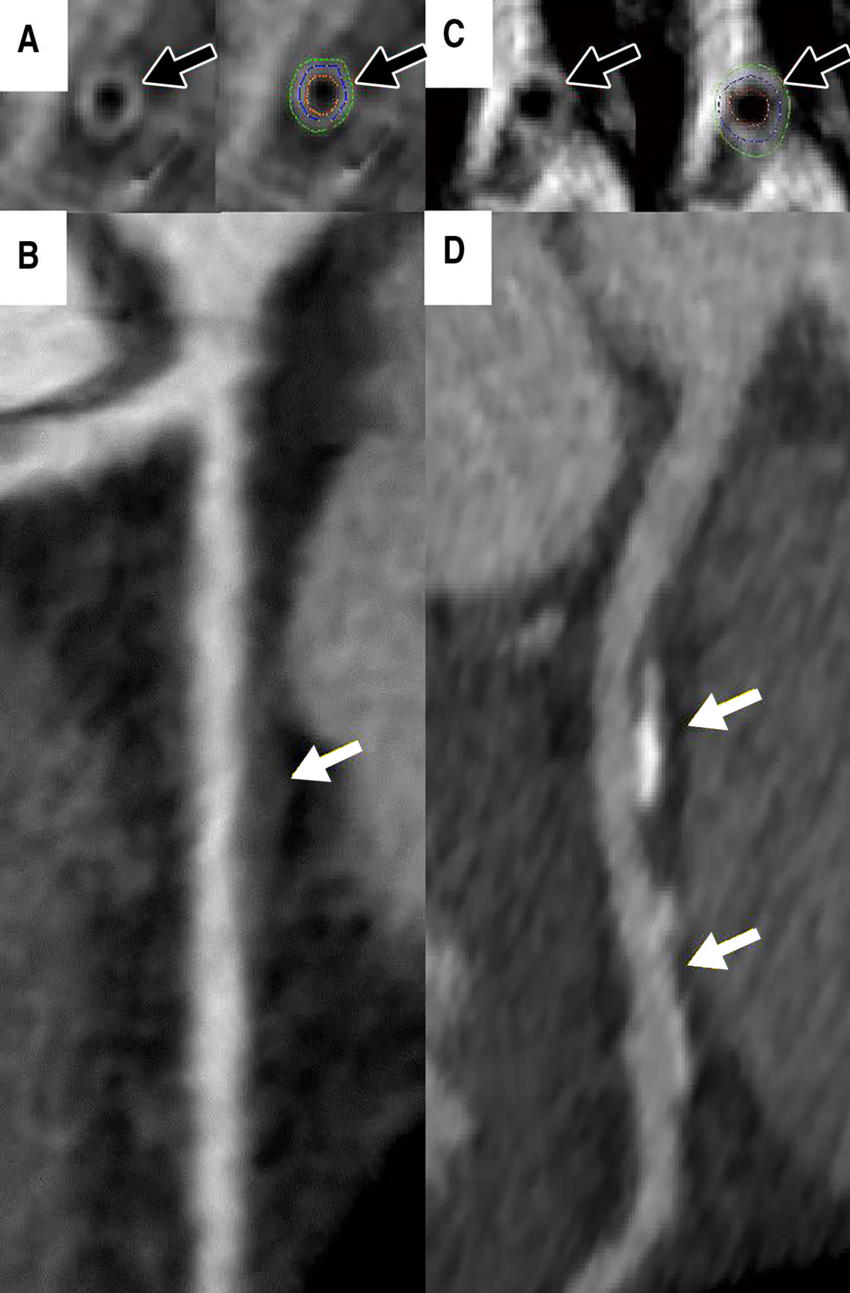

Figure 3. Coronary vessel wall CT angiographic images (multiplanar reformatted stretch view). Images in a 46-year-old asymptomatic woman show, A, measured vessel wall thickness of 1.3 mm (black arrows) and, B, noncalcified plaque (white arrow) in the proximal left anterior descending coronary artery. Coronary CT angiographic images in the left anterior descending artery in a 44-year-old asymptomatic woman show, C, thicker coronary vessel wall (black arrows) and, D, coronary artery disease (white arrows).